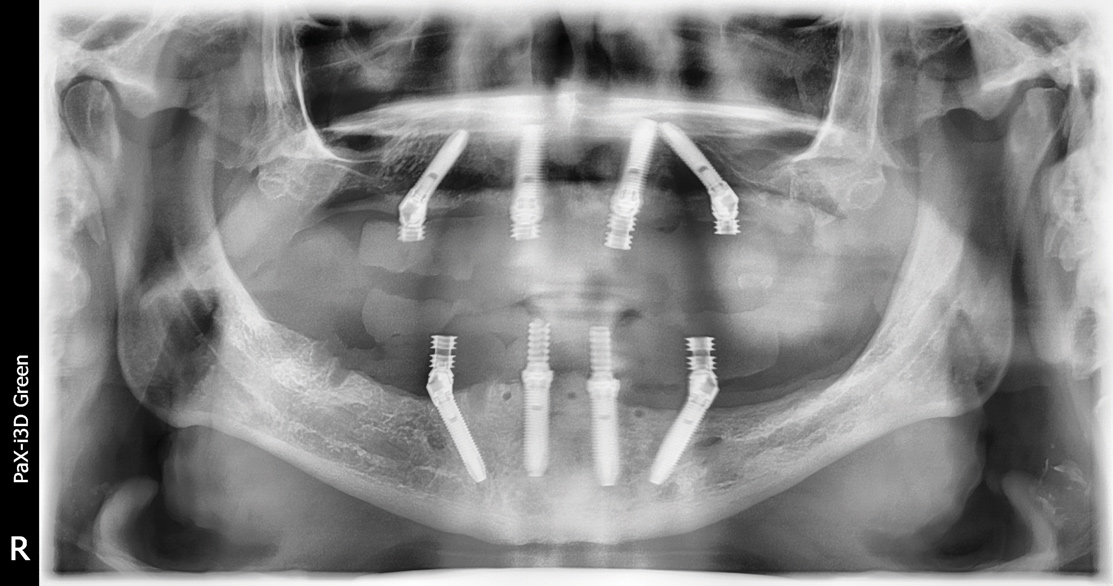

Figure 13: The left posterior implant had low primary stability and was elected not to be connected to the conversion prosthesis, as shown in the post-operative panoramic radiograph.

Figure 13